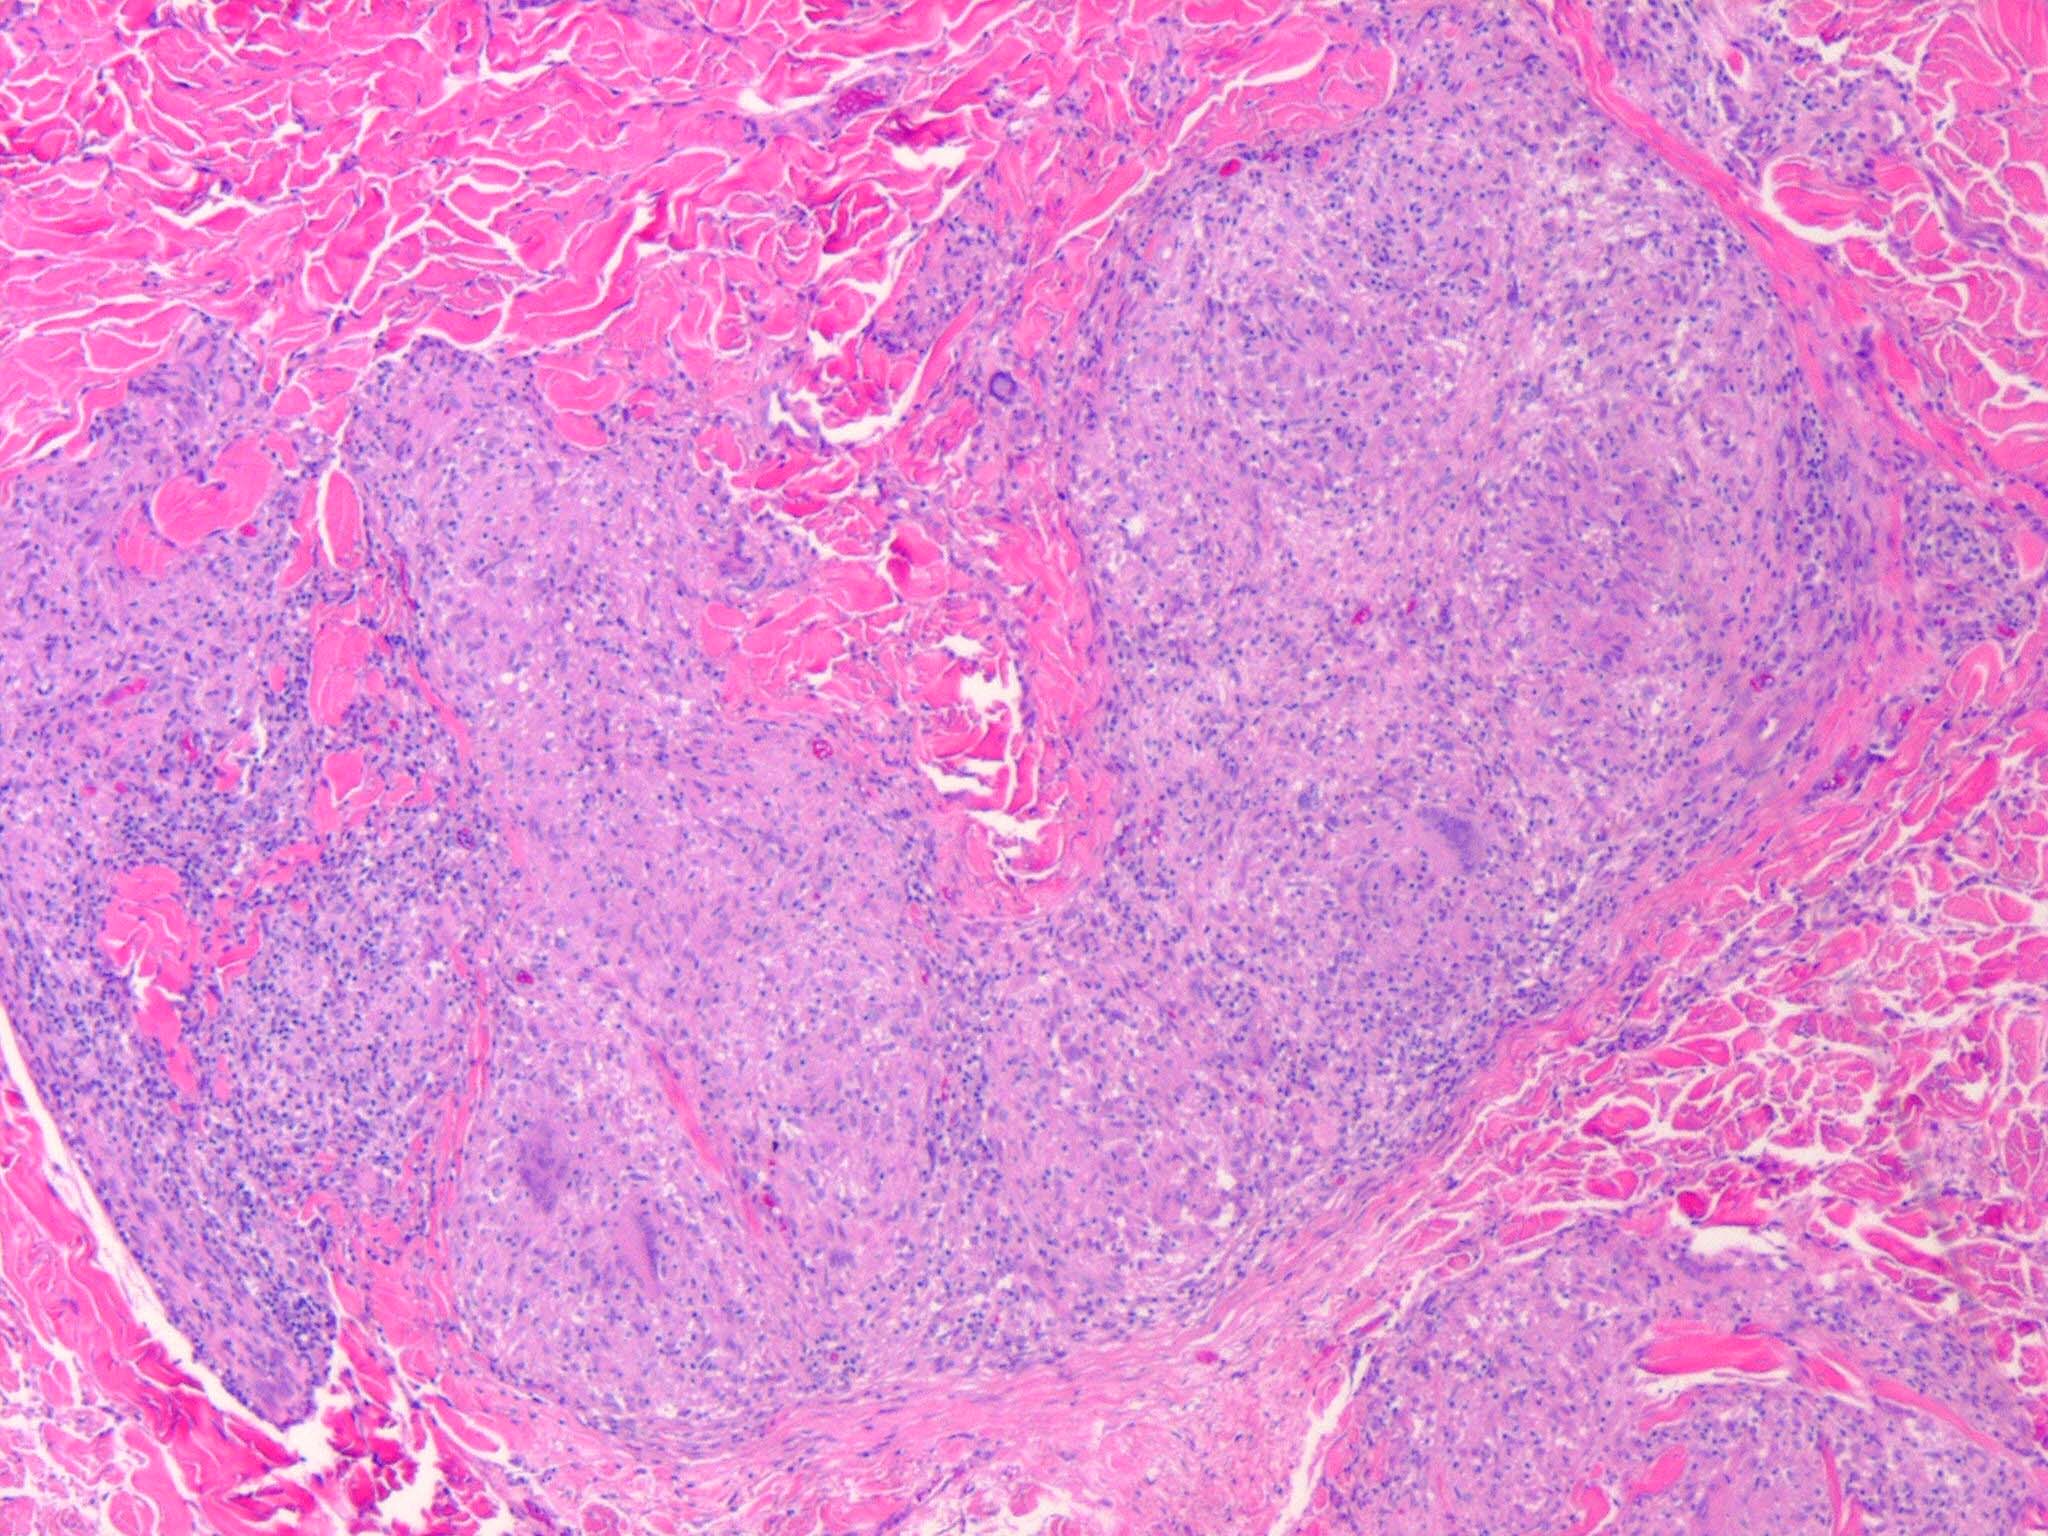

Like lesions in other organs, the cutaneous lesions of chronic, persistent sarcoidosis are characterized by the presence of circumscribed collections of epithelioid histiocytes-so-called epithelioid cell tubercles-which show little or no necrosis .

The papules, plaques, and lupus pernio-type lesions show variously sized aggregates of epithelioid cells scattered irregularly through the dermis with occasional extension into the subcutis (. In the erythrodermic form, the infiltrate shows small granulomas in the upper dermis intermingled with numerous lymphocytes

hypopigmented sarcoid may reveal granulomas, which may have a perineural component or fail to reveal granulomas . In subcutaneous nodules, larger epithelioid cell tubercles lie in the subcutaneous fat .

In typical cutaneous lesions of sarcoidosis, the well-demarcated islands of epithelioid cells contain few, if any, giant cells. Those that are present are usually of the Langhans type. A moderate number of giant cells can be found in old lesions. These giant cells may be large and irregular in shape. In a minority of cases, giant cells contain asteroid bodies or Schaumann bodies . Asteroid bodies , which are more common, are star-shaped eosinophilic structures that, when stained with phosphotungstic acid-hematoxylin, produce a center that is brown-red with radiating blue spikes . Schaumann bodies are round or oval, laminated, and calcified, especially at their periphery. They stain dark blue because of the presence of calcium. Neither of these two bodies is specific for sarcoidosis: They have been observed in a variety of other granulomas, including those of leprosy, tuberculosis, foreign-body reactions, and necrobiotic xanthogranuloma .

Classically, sarcoid has been associated with only a sparse lymphocytic infiltrate, particularly at the margins of the epithelioid cell granulomas . Because of the scarcity of lymphocytes, the granulomas have been referred to as “naked” tubercles. However, lymphocytic infiltrates in sarcoid may occasionally be dense, as in tuberculosis . Occasionally, small foci of fibrin or necrosis showing

eosinophilic staining is found in the center of some of the granulomas . A reticulum stain of sarcoid reveals a network of reticulum fibers surrounding and permeating the epithelioid cell granulomas. If the granulomas of sarcoidosis involute, fibrosis extends from the periphery toward the center, with gradual disappearance of the epithelioid cells . Fibrosis, however, is minimal to absent in most examples of sarcoidosis, with the exception of the morpheaform variant, where it is prominent {191}. Other features that may sometimes be seen include elastophagocytosis, increased dermal mucin, and lichenoid inflammation .